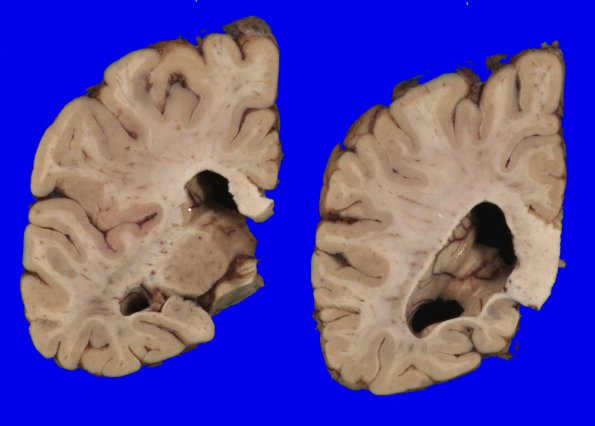

Coronal slicing revealed mild dilatation of the lateral ventricles with rounding of the angles, increased space in the inferior horns, and small hippocampi.